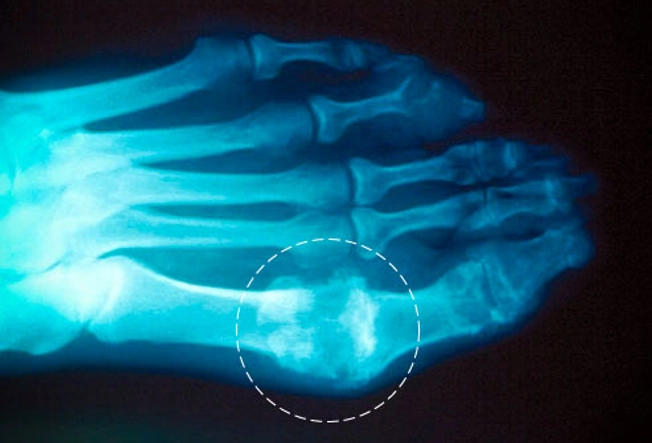

통풍의 대표적인 증상은 급격한 발작성 관절통입니다. 이러한 관절통은 대개 한쪽 발가락의 근처에 위치한 무릎, 발목, 발가락, 손목 등의 관절에서 발생하며, 강한 통증과 함께 염증이 발생하여 발적이 생길 수 있습니다. 발적은 종종 발가락을 둘러싸며 발생하며, 대개 하나 또는 두 개의 관절에서 동시에 나타납니다. 발적은 대개 몸의 상하층에 대한 분포도가 높습니다.

통풍은 혈액 내 요산 수치의 상승으로 인해 발생합니다. 요산은 식사와 관련된 인슐린에 의해 조절되며, 요산의 과다 생성 또는 제거 부전이 발생하면 혈액 내 요산 수치가 증가하게 됩니다. 이러한 상황에서, 혈액 내 요산 결정이 관절 주변의 소프트 조직에 쌓이면 염증을 일으키고, 통증과 붓기 등의 증상이 나타납니다.

통풍을 진단하기 위해서는 혈액검사, 요산 검사, 관절유액 검사 등이 필요합니다. 혈액 검사에서는 혈액 내 요산 수치를 측정하고, 요산 결정을 발견할 수 있습니다. 요산 검사에서는 소변 검사, 24시간 요중 요산 측정 등을 통해 요산의 생성 및 제거 기능을 평가합니다. 관절유액 검사에서는 염증 유무를 확인하고, 필요한 경우 관절 유액 내 요산 결정을 확인할 수 있습니다. 이러한 검사를 통해 증상을 보이는 환자의 진단을 정확하게 하여 적절한 치료 계획을 수립할 수 있습니다.